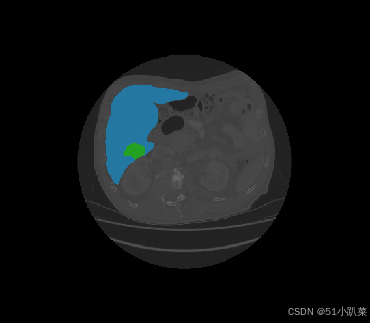

基于Unet分割医学2D3D图像

器官分割和三维重建